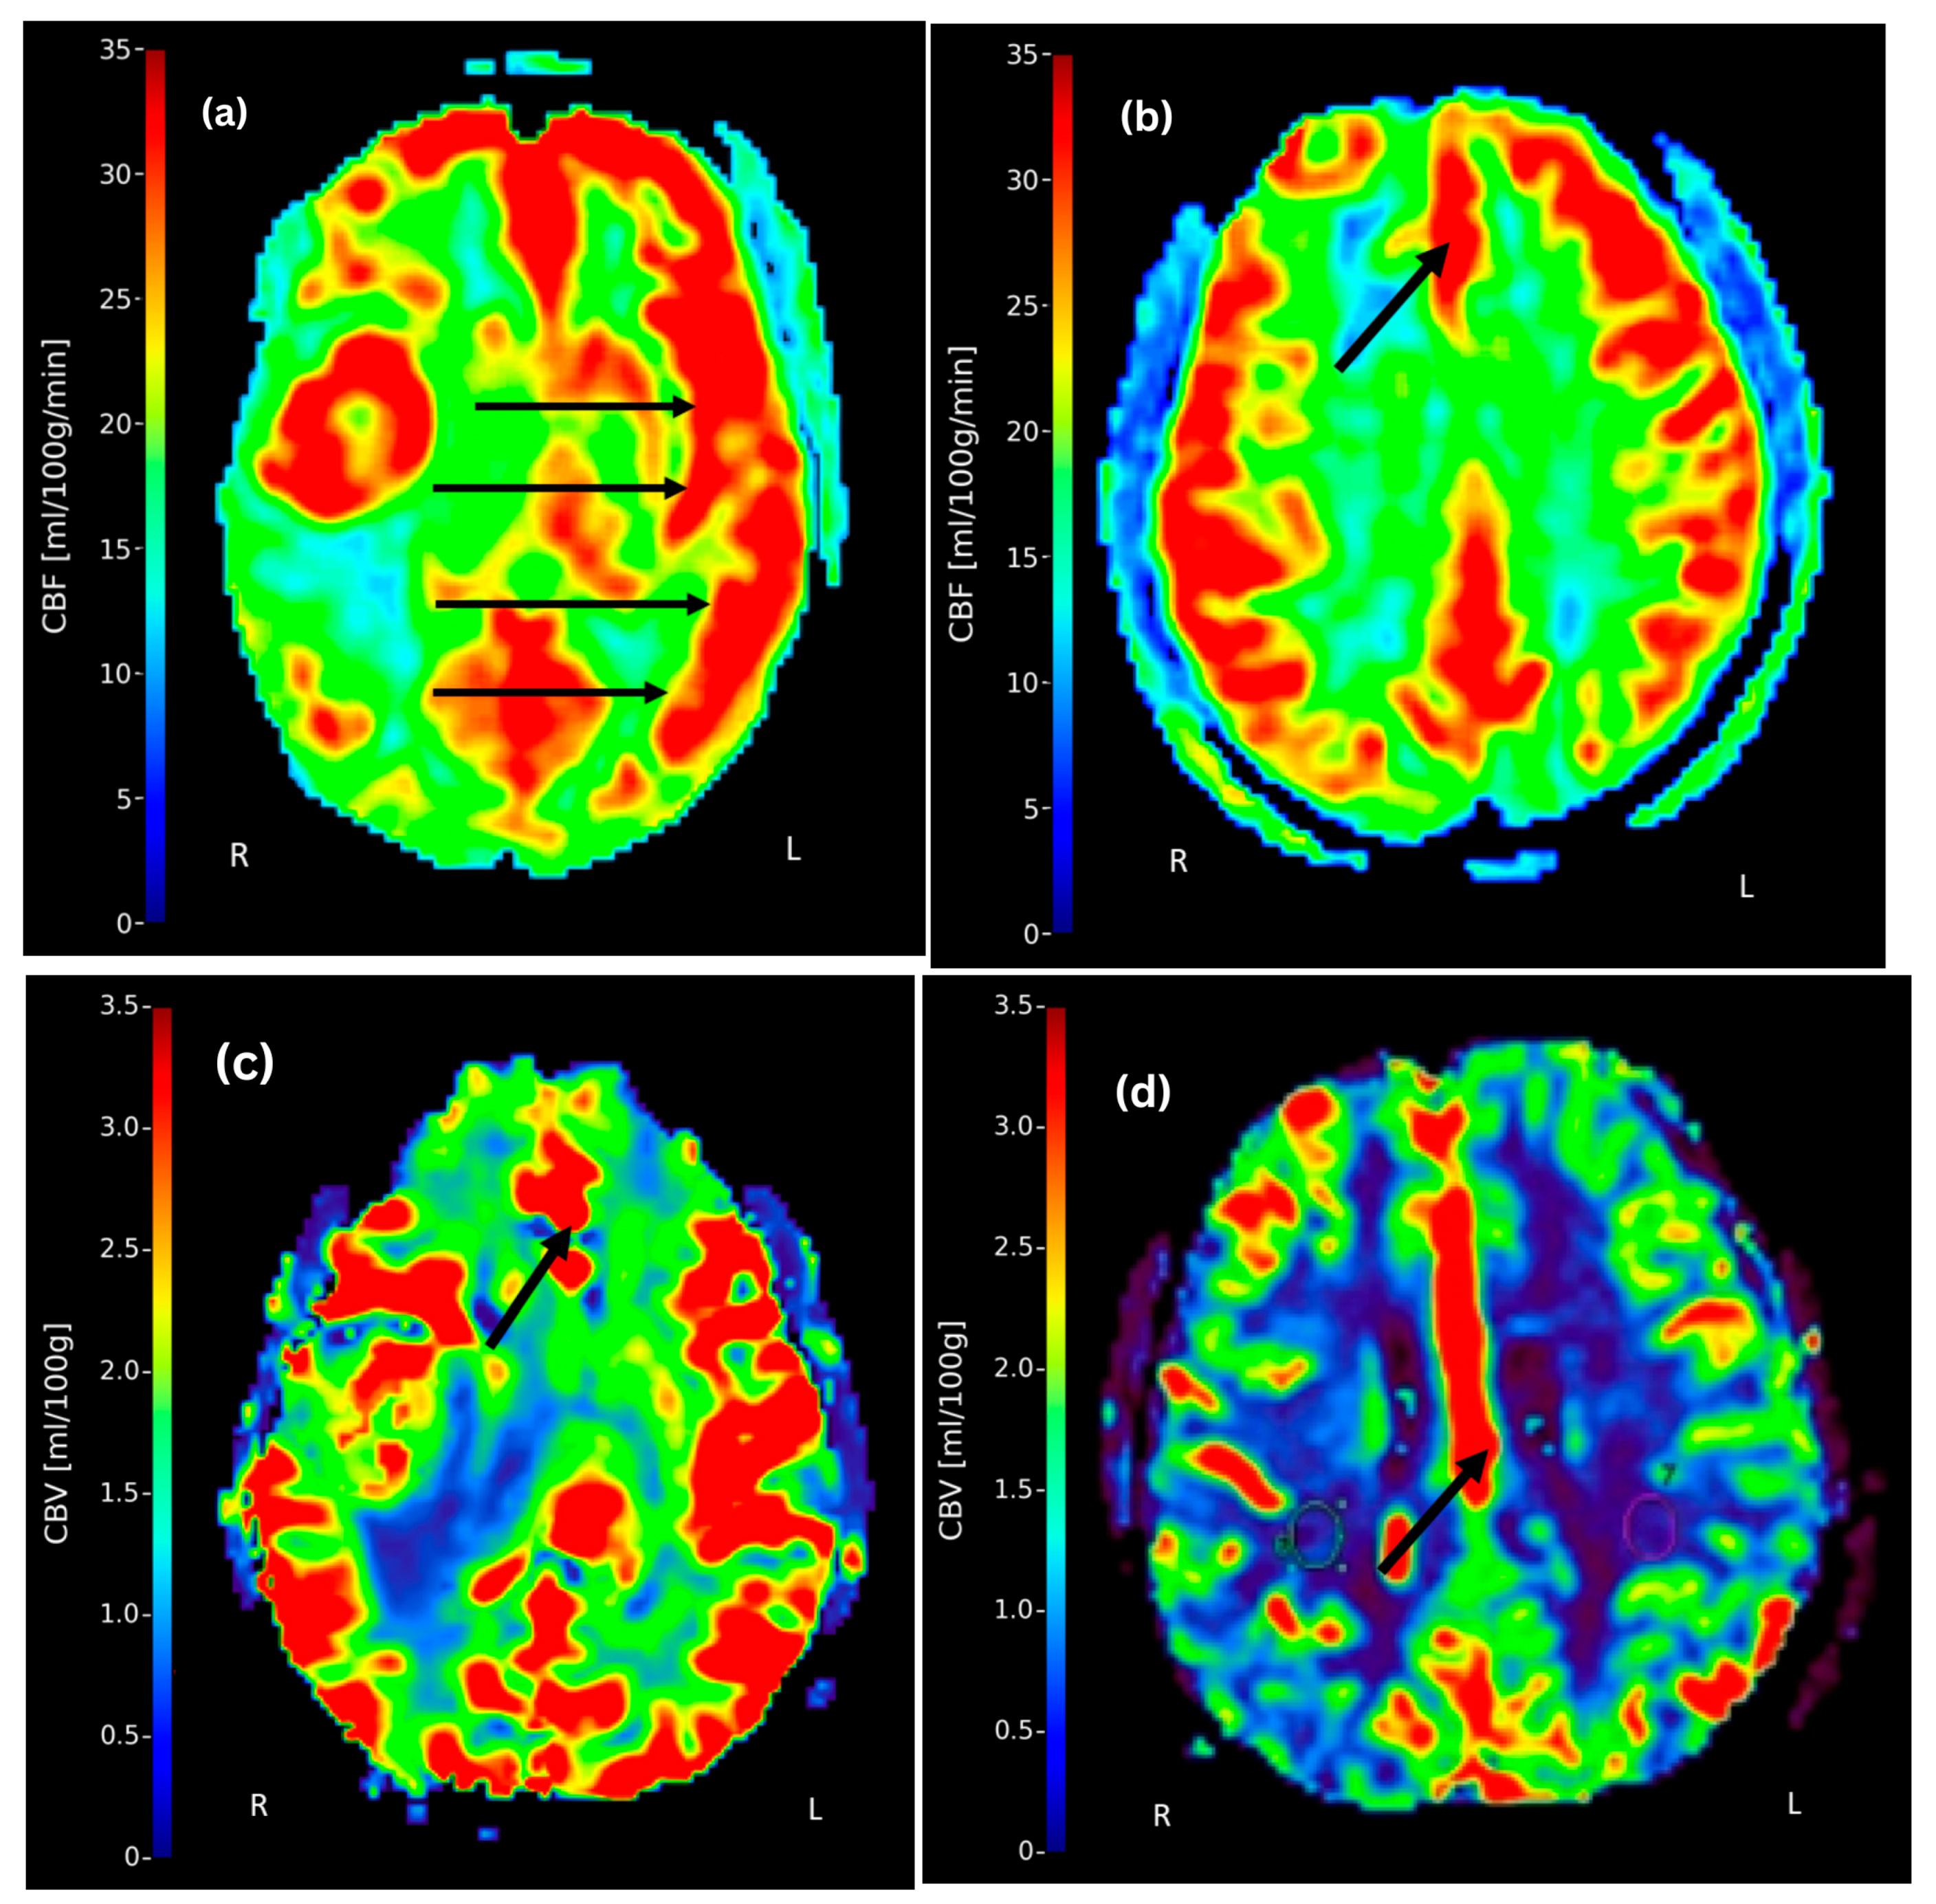

The range of CBF and CBV across major cerebral arterial territories is presented in Table 4, with mean values visualized in Figure 2. The data demonstrate measurable perfusion variability between the left and right hemispheres, as well as across different vascular territories. A descriptive analysis of CBF and CBV values indicated a consistent pattern of left-sided dominance, which was particularly evident in the MCA and ACA regions as shown in Figure 3. Representative DCE-MRI perfusion maps illustrating these patterns are shown in Figure 4, where panels (a) and (b) highlight elevated CBF in the left MCA and ACA territories, respectively. Panels (c) and (d) demonstrate lateralization of CBV, with reduced perfusion in the right ACA territory, visually confirming the descriptive trends reported in Table 4. These asymmetrical perfusion patterns suggest hemodynamic differences between hemispheres that may correlate with stroke lateralization, which may vary with stroke location and severity, warranting further investigation to determine clinical significance.

Paired t-tests conducted between contralateral arterial regions (i.e., left and right MCA, ACA, and PCA) revealed statistically significant differences in CBF for all comparisons (right vs. left MCA: p = 0.00197; right vs. left PCA: p = 0.000105; right vs. left ACA: p = 0.000013). All p-values remained significant after applying a Bonferroni correction for multiple comparisons (adjusted α = 0.0167), confirming robust lateralization of CBF across hemispheres in ischemic stroke patients. These findings are visually supported by the perfusion maps in Figure 4, which demonstrate left-sided dominance in CBF. These results from the paired t-tests highlight the lateralization of CBF between contralateral hemispheres.

Figure 4. Representative post-contrast DCE-MRI T1-weighted axial slices acquired within 48 h of stroke symptom onset from four different ischemic stroke patients. Panels (ad) display colour-coded perfusion maps quantifying cerebral blood flow (CBF; range: 0–35 mL/100 g/min) and cerebral blood volume (CBV; range: 0–3.5 mL/100 g). The parameters used for image acquisition and their post-processing are described in Section 2.4. (a) Image from a 63-year-old patient showing left-sided dominance of CBF in the middle cerebral artery (MCA) territory, as indicated by arrows. (b) Image from a 51-year-old patient showing elevated CBF in the left anterior cerebral artery (ACA) territory (arrow). (c,d) images from 26- and 75-year-old patients, respectively, showing high CBV in the left ACA territory (arrow). These visual findings are consistent with the results of the paired t-test analyses, which demonstrated significant hemispheric asymmetries in CBF and the descriptive analysis of CBF and CBV. The arrows highlight perfusion dominance or reduction regions, visually confirming the hemispheric asymmetries and perfusion variations quantified through descriptive (Table 3 and Table 4) and inferential (Table 5) statistical analyses.